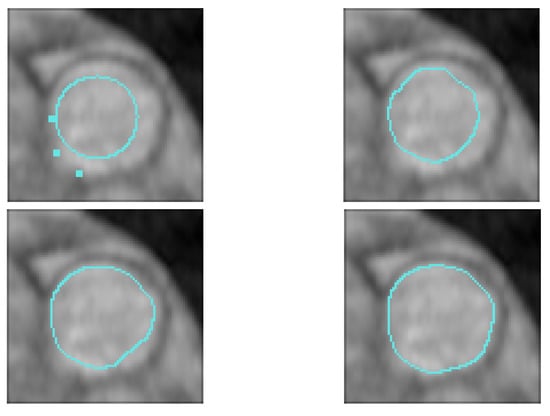

An example of the segmentation of a pulmonary artery with a curve to interpolate is given in Figure 10. A part of this artery is difficult to segment since its bottom left is always located in a blurred zone.

Figure 10. Blood vessel image, user-defined constraint (top right), initial contour (bottom left) and final (bottom right) contours. Let us note that we have successfully segmented the complete image sequence.